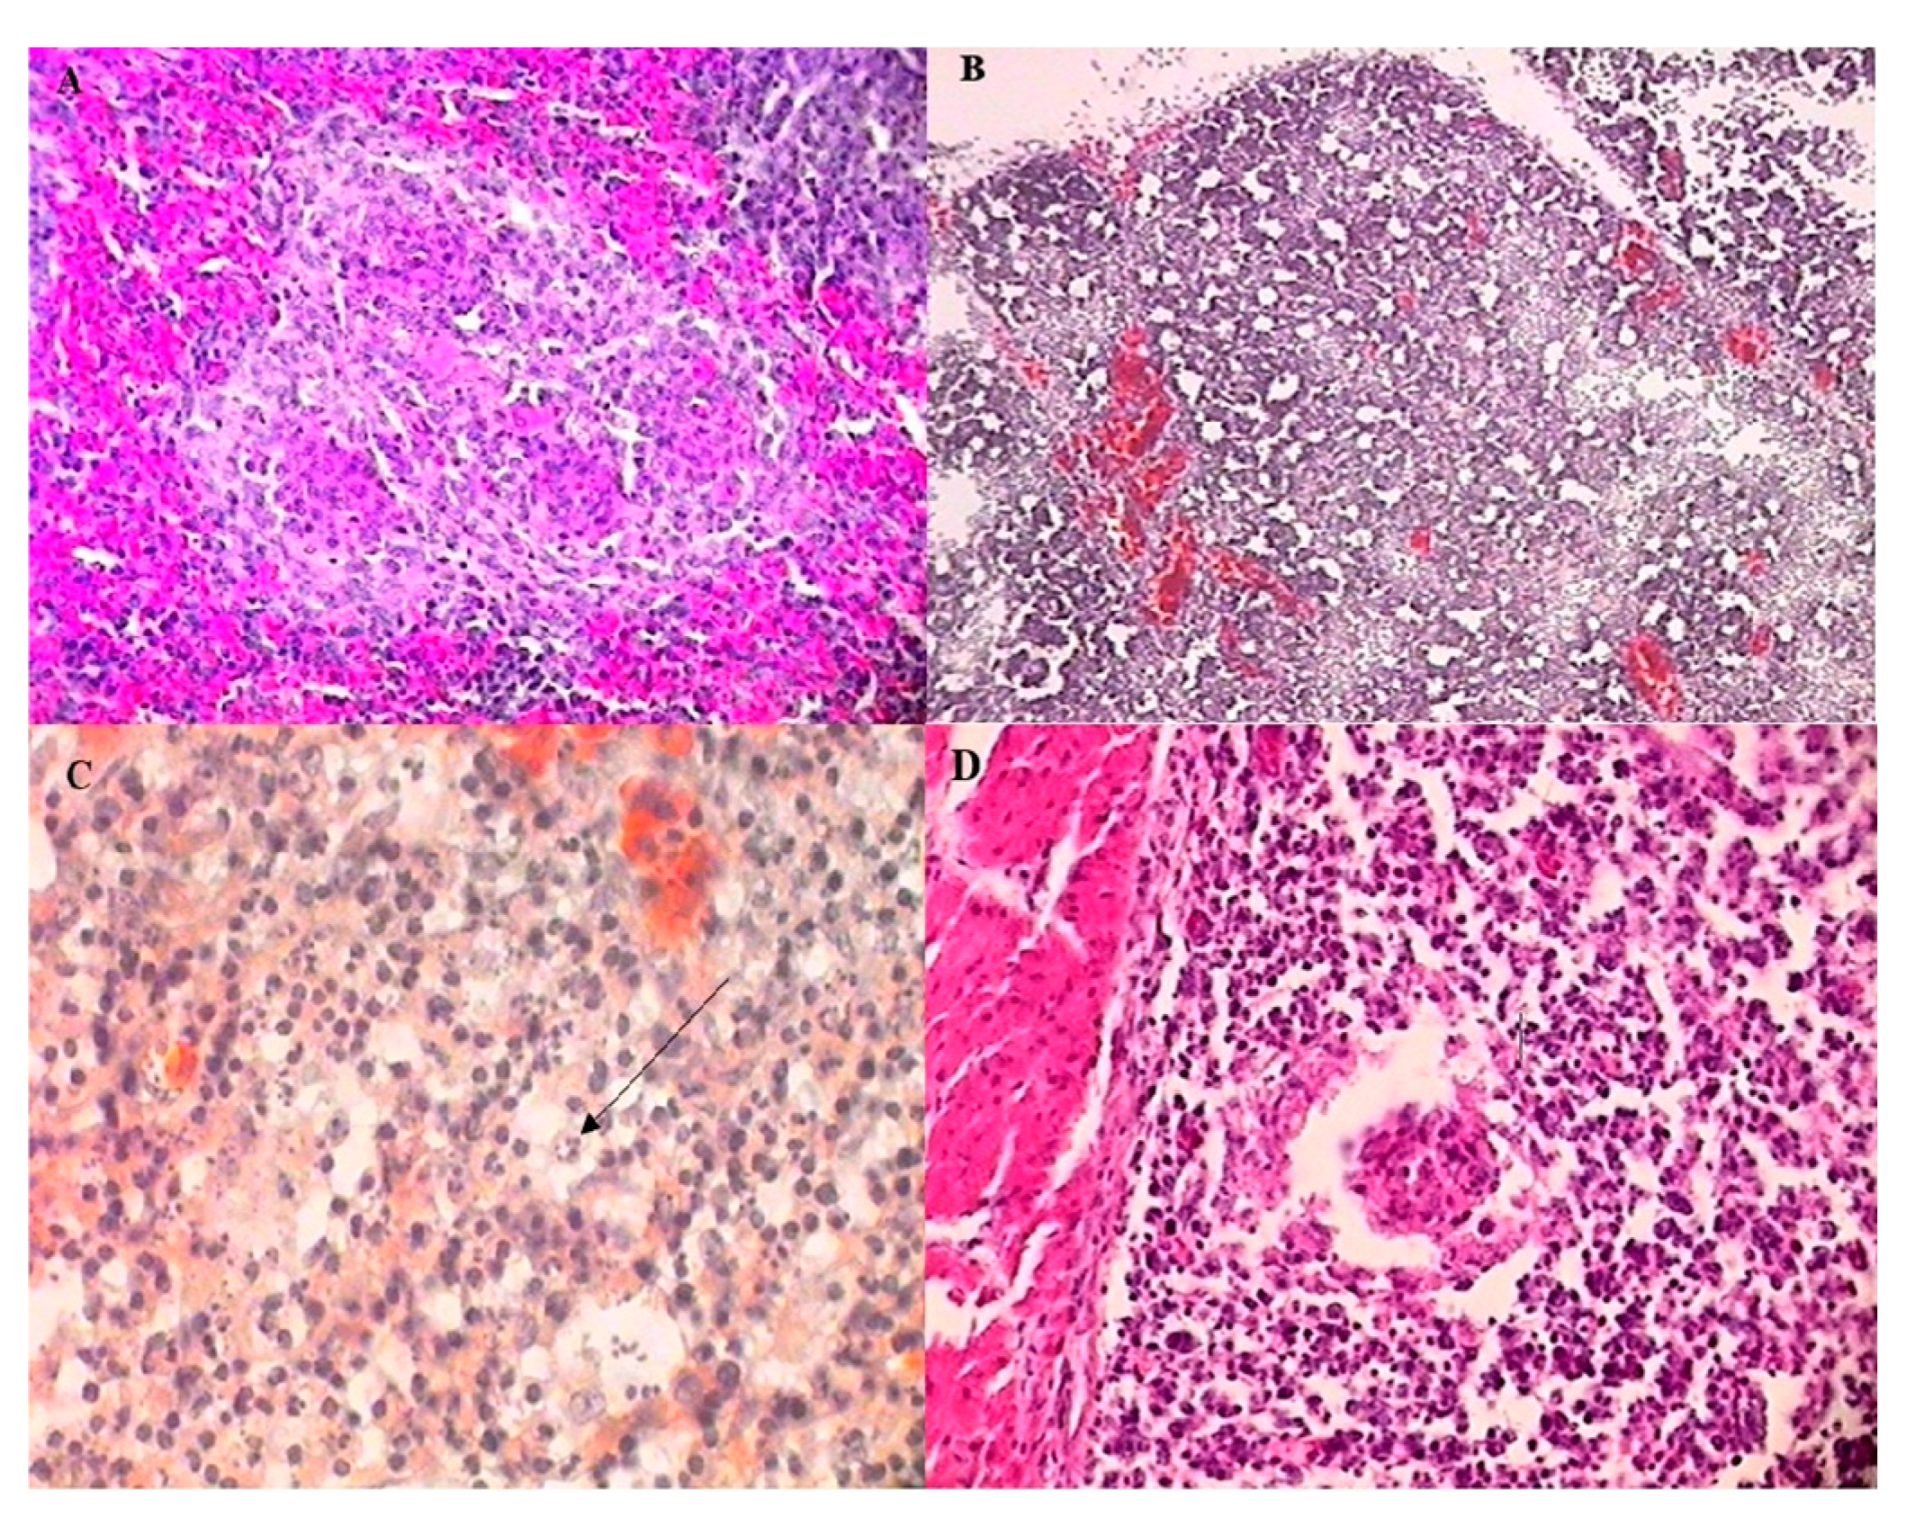

3.4. Microscopic Lesions

3.4.1. Bursa of Fabricius

3.4.2. Spleen

3.4.3. Thymus

3.4.4. Caecal Tonsil